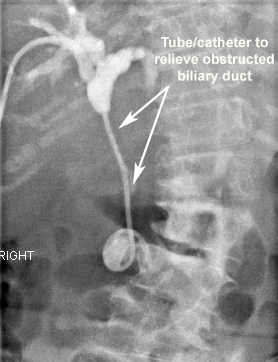

Cancer arising originally from the liver or spread to the liver from cancer elsewhere can cause obstruction to the normal flow of digestive juice (bile) from liver into the bowel. Usually, patients are known to have a cancer or occasionally present to their doctor with symptoms related to this for the first time.

Usually, patients may present with worsening jaundice (yellowing of the white part of the eyes), itching, dark urine and pale/white stools and also sometimes with abdominal pain. The symptoms will worsen and impact on the quality of life if the obstruction is not relieved.

If you or family members have advanced cancer of the liver, which is causing worsening jaundice, this may be treatable with stenting the bile tube/duct which can reduce the yellowish skin discoloration and intractable itching. This may significantly improve the quality of life. Please ask your doctor for relevant information.